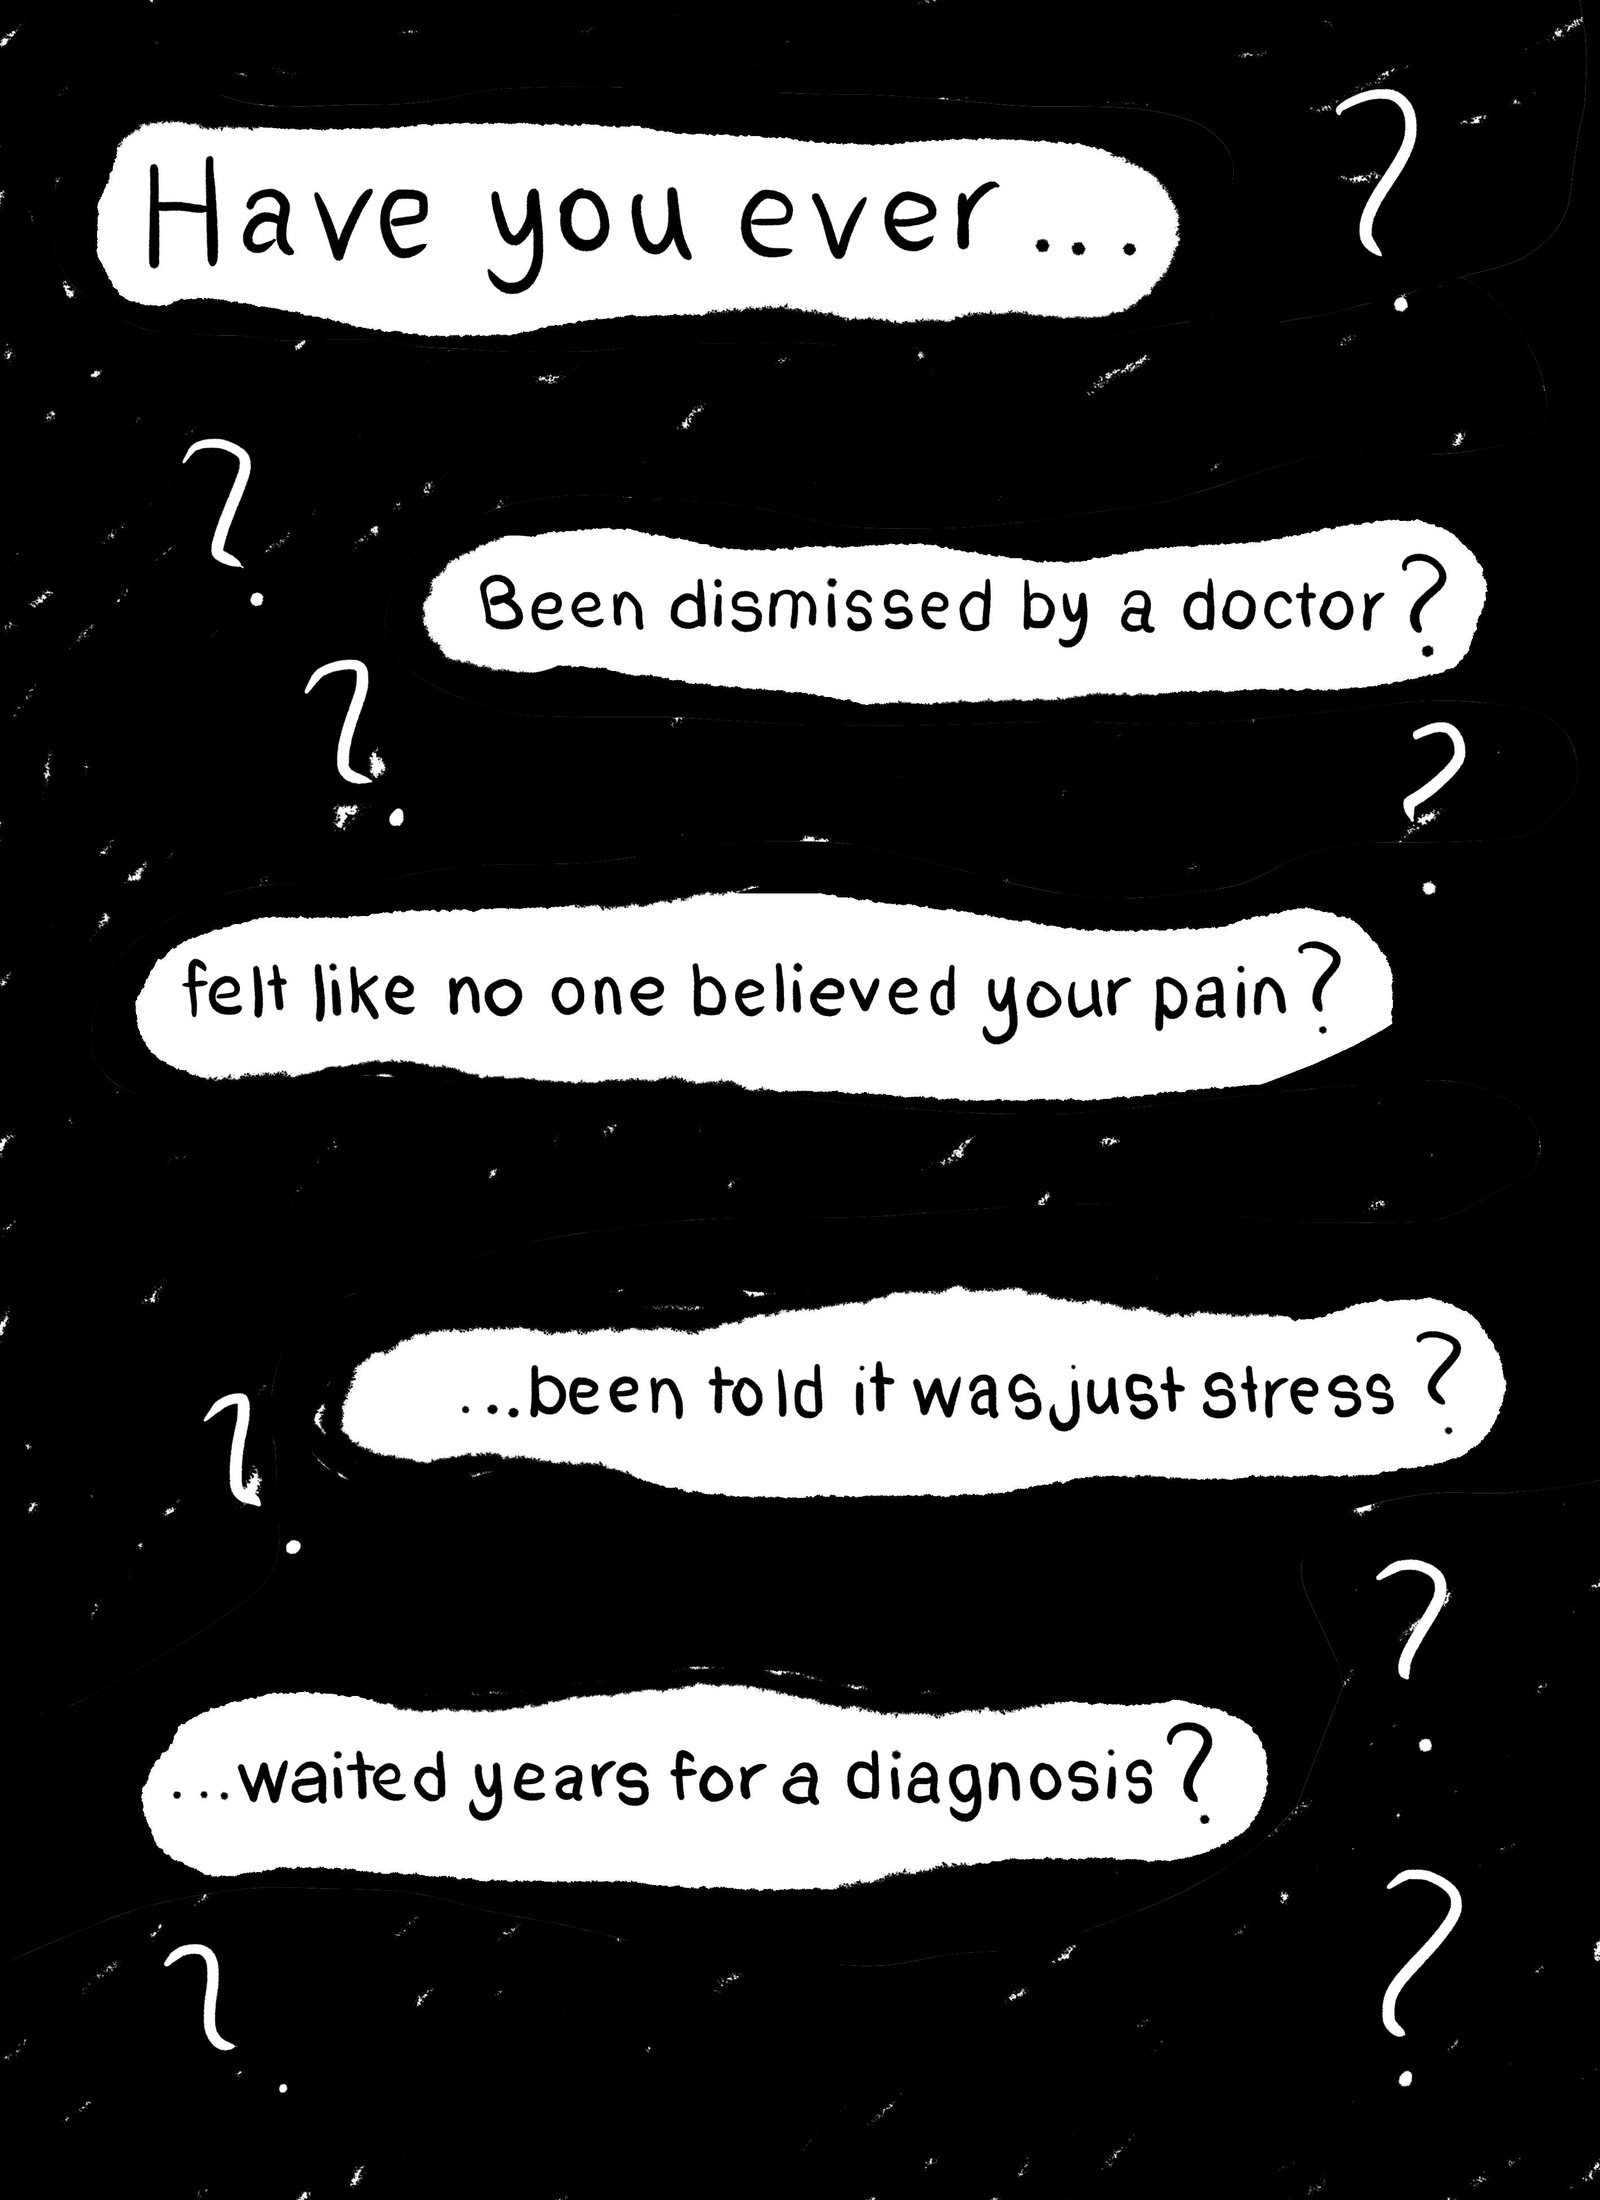

The P.O.V of the female patient, the reality of what is happening.

We believe you